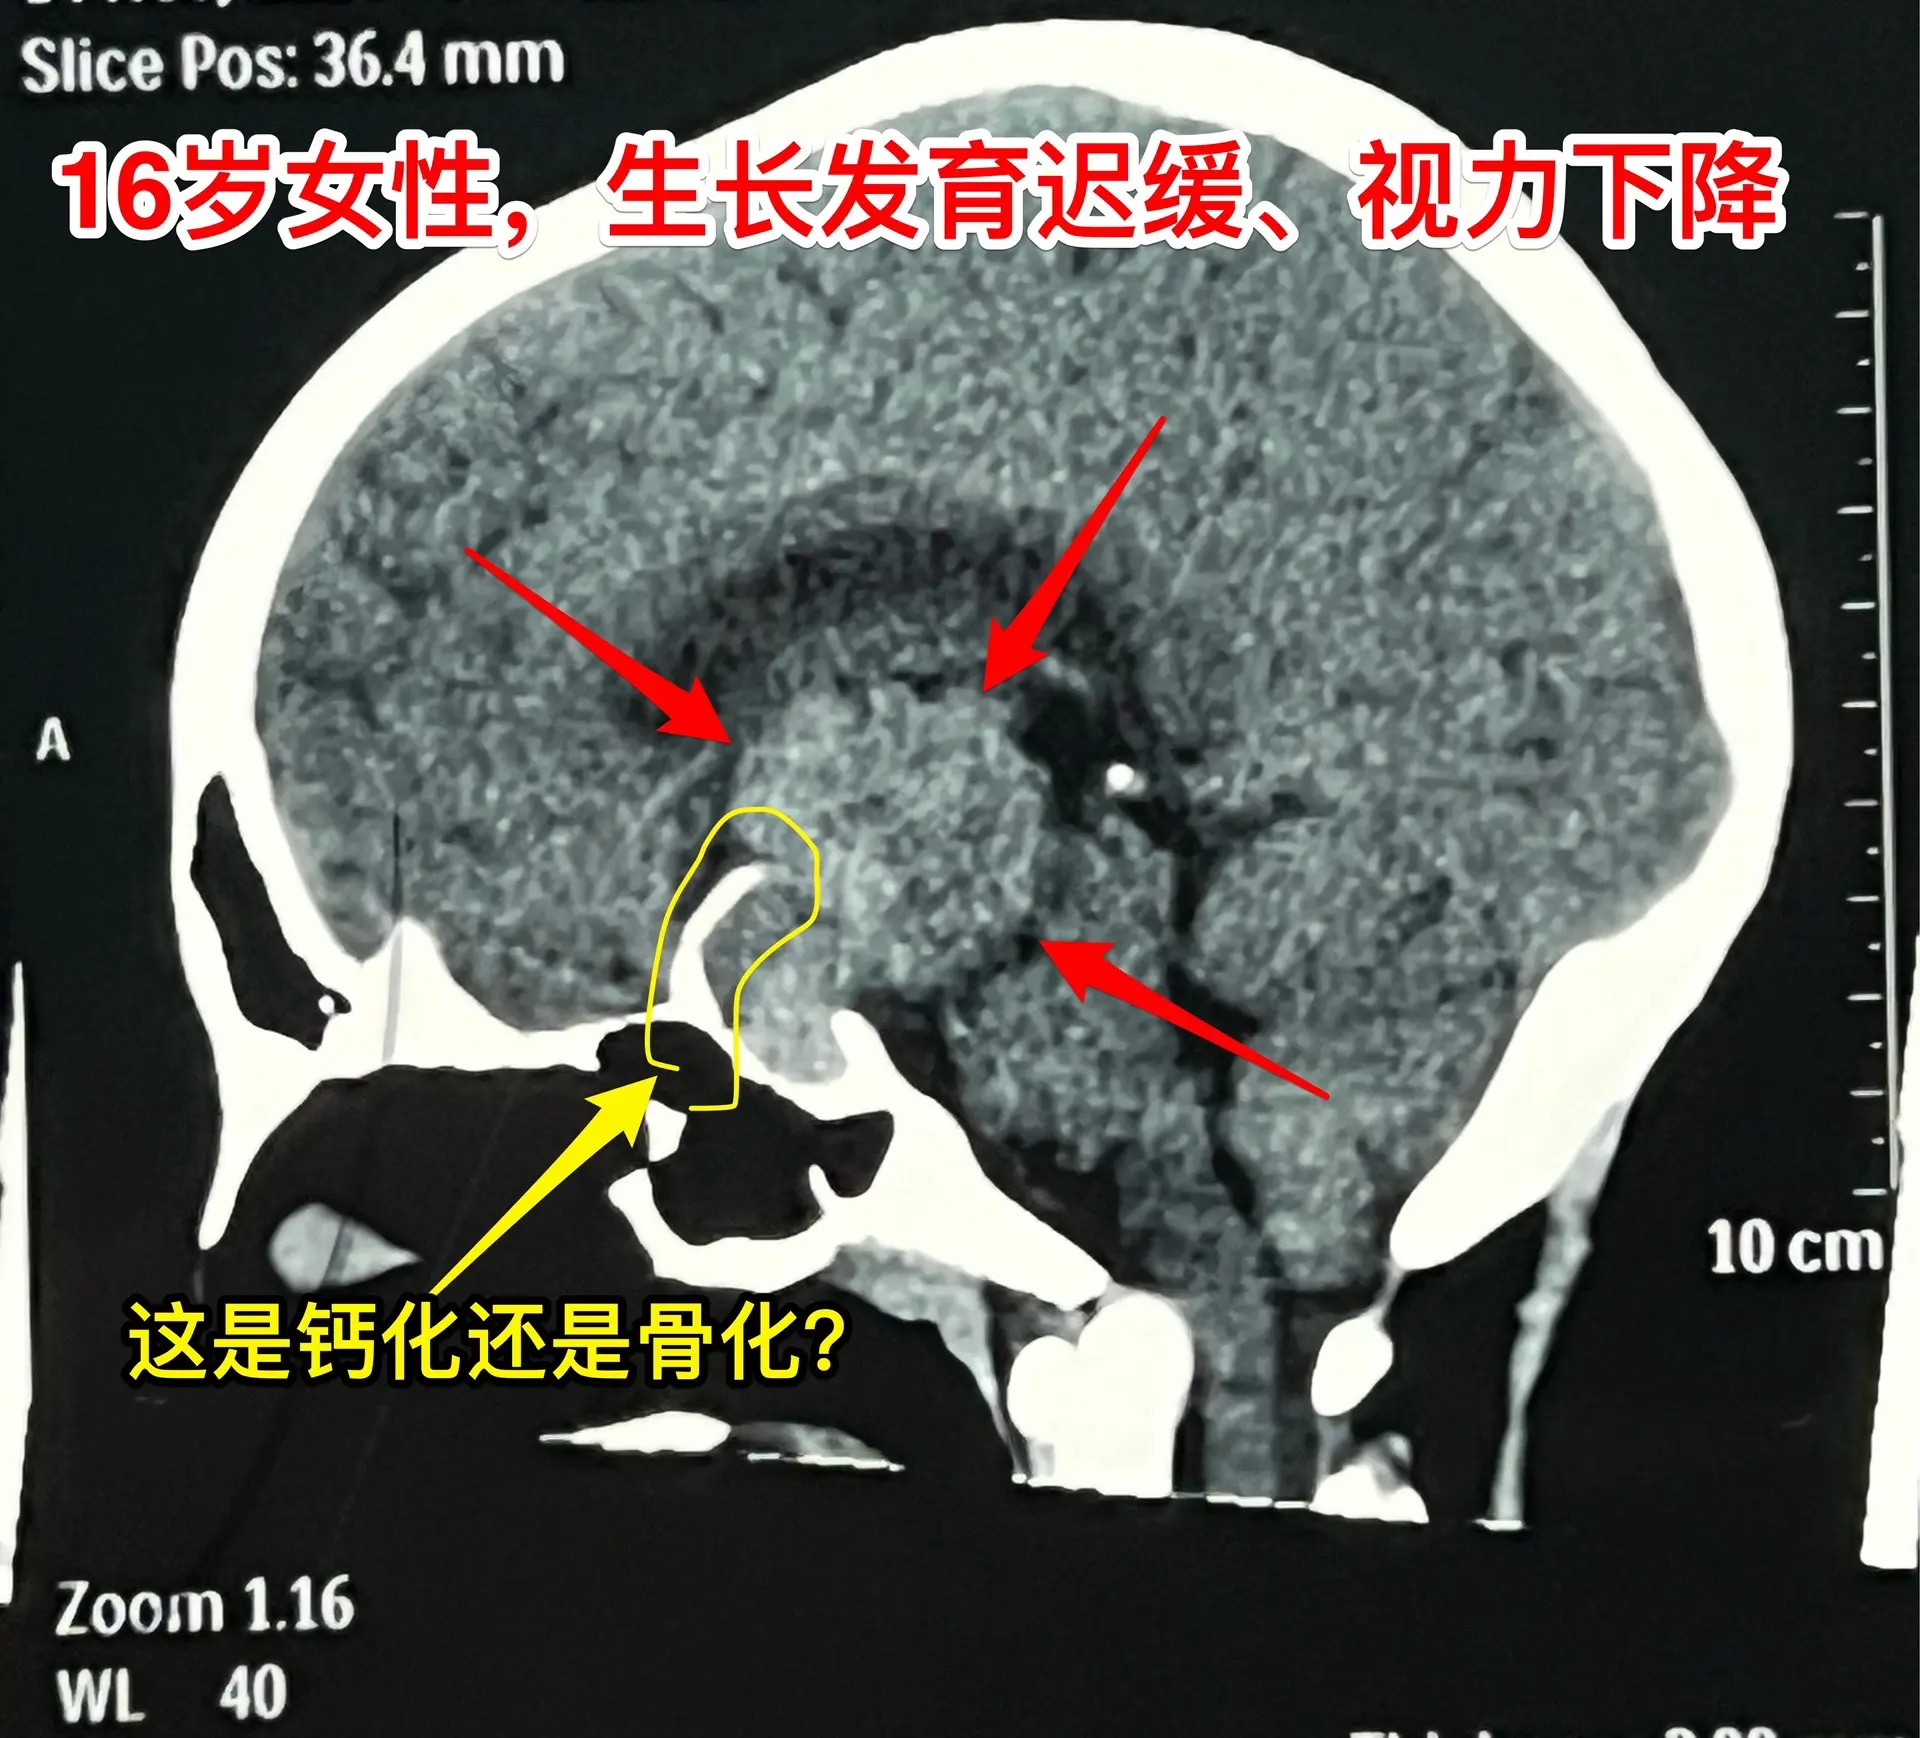

16岁女生在10岁时就有生长发育迟缓症状。16岁衡阳市女生,现在身高才120厘米,体重才21公斤。初中毕业后就辍学了! 她在10岁时就有生长发育迟缓症状,到医院去检查发现生长激素分泌不足。没有找出具体原因,也没有注射生长激素治疗。 近一年有头痛症状,视力也下降了。作磁共振发现长了脑部肿瘤,才到北京来找我作手术。肿瘤体积大,没有钙化,是颅咽管瘤吗? 昨天在手术过程中,取出病变标本作快速冰冻病理检查,报告为乳头型颅咽管瘤。这种类型的颅咽管瘤在小孩子中十分罕见。 我多次提醒家长,如果发现小孩子的生长发育有异常,要尽早到医院去检查,找出原因,尤其是针对脑部要作磁共振检查,排除脑部肿瘤。对于生长激素缺乏者,不能不管原因,轻易注射生长激素治疗。